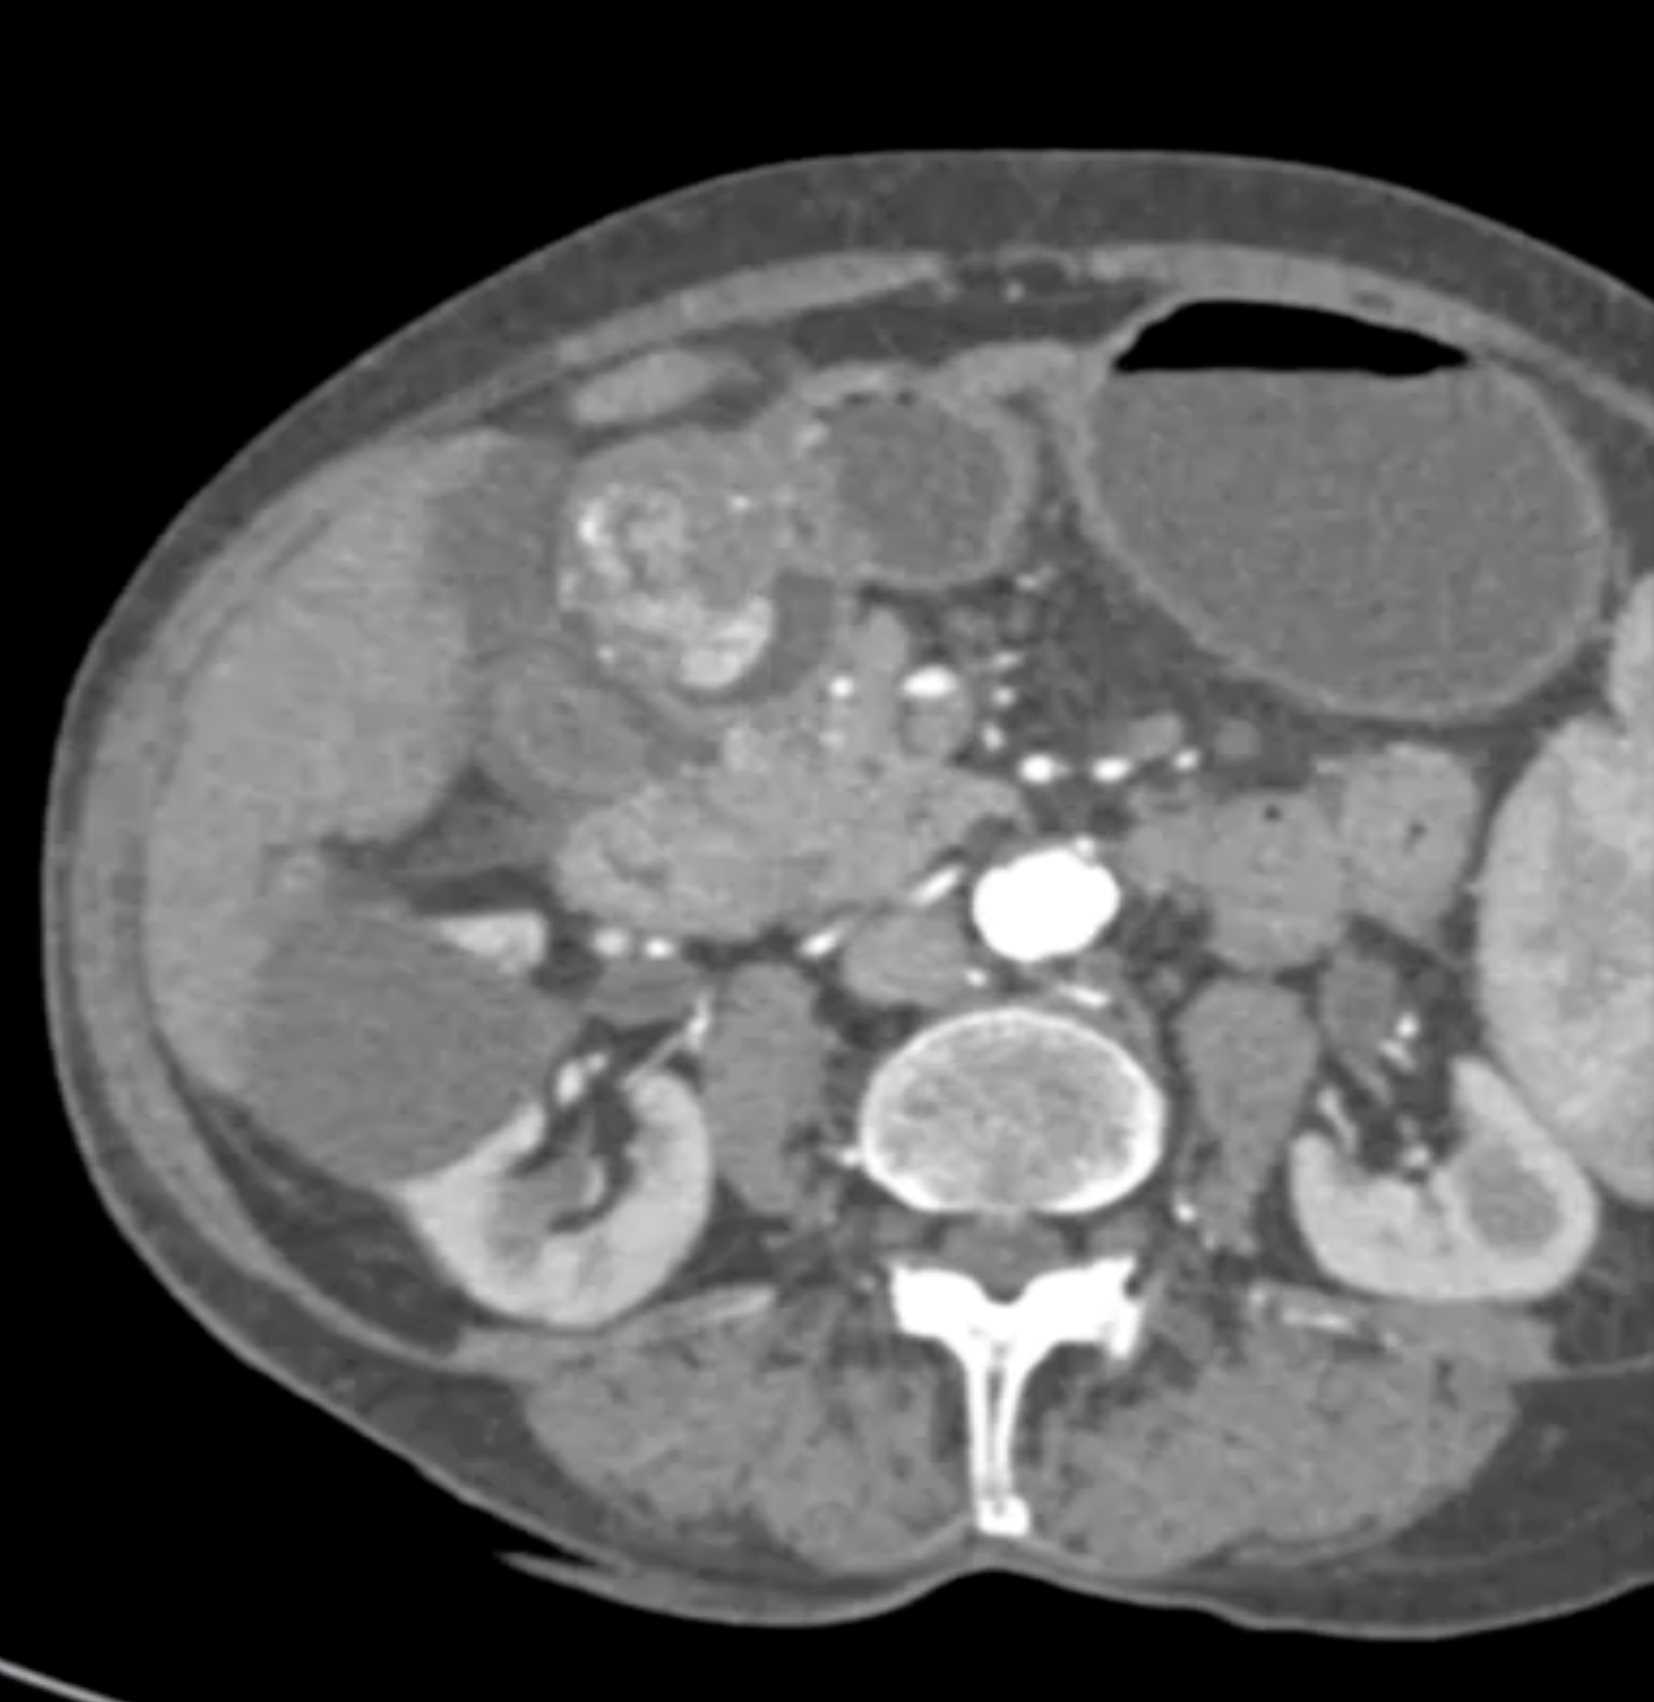

Watermelon Stomach (Gastric Antral Vascular Ectasis)